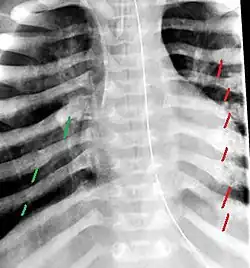

The material factual allegations of the amended complaint are as follows. Plaintiff was born on May 14, 1970. On repeated occasions during the first year of her life she was severely beaten by her mother and the latter's common law husband, one Reyes. On April 26, 1971, when the plaintiff was eleven months old, her mother took her to the San Jose Hospital for examination, diagnosis, and treatment. The attending physician was defendant Dr. Flood, acting on his own behalf and as agent of the defendant San Jose Hospital. At the time, the plaintiff was suffering from a comminuted spiral fracture of the right tibia and fibula, which gave the appearance of having been caused by a twisting force. Plaintiff's mother had no explanation for this injury. Plaintiff had bruises over her entire body. In addition, she had a non-depressed linear skull fracture which was then in the process of healing. Plaintiff demonstrated fear and apprehension when approached. Inasmuch as all plaintiff's injuries gave the appearance of having been intentionally inflicted by other persons, she exhibited the medical condition known as the battered child syndrome.

The complaint avers that as a proximate result of the foregoing negligence plaintiff was released from the San Jose Hospital without proper diagnosis and treatment of her battered child syndrome, and was returned to the custody of her mother and Reyes who resumed physically abusing her until she sustained traumatic blows to her right eye and back, puncture wounds over her left lower leg and across her back, severe bites on her face, and second and third degree burns on her left hand.

On July 1, 1971, plaintiff was again brought in for medical care, but to a different doctor and hospital. Her battered child syndrome was immediately diagnosed and reported to local police and juvenile probation authorities, and she was taken into protective custody. Following hospitalization and surgery she was placed with foster parents, and the latter subsequently undertook proceedings to adopt her. Plaintiff's mother and Reyes fled the state, but were apprehended, returned for trial, and convicted of the crime of child abuse.[3]